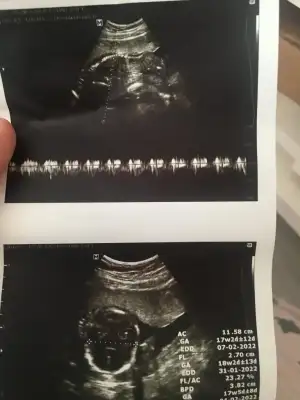

dr soylemeden siz gorun genital nub teorisi ( bebegin cinsiyeti)

Emin olamadim kız gibi sankiBizde bugün kontrolden çıktık 12+3 haftalığız ,doktor cinsiyet için emin olamadı resimlerden siz yorum yapabilirmisiniz

Erkek sanki sizin usgler net değilBu ultrason resmini gore bellimi acaba nub bi bakarmisiniz ikra meyra

Net değil USG emin olamadımIkra meyra bu görüntümüz var ama sırtı dönük tahmin yapabilecek misin bu ultrasonda canım teşekkürler

Canım bi bakar mısın yandan net görüntü yok maalesef 18 haftalık doktor erkek dedi ikinci resimde işaretlediği kısma pipi dedi sence de erkek mi bundan önce ki doktor kıza benzetmiştiKız gibi

Kız gibiKizlar bu da benim yavrum 12+3 sizce nedir çok merak ediyorumEki Görüntüle 2910088

Canım bakar mısın benim attığımı daCanım bi bakar mısın yandan net görüntü yok maalesef 18 haftalık doktor erkek dedi ikinci resimde işaretlediği kısma pipi dedi sence de erkek mi bundan önce ki doktor kıza benzetmişti

Emin olamadım sanki erkek gibi

Doktor da emin değil ama erkek gibi sanki dediEmin olamadım sanki erkek gibi

Merhaba bana da tahmin yapabilir misiniz?Erkek ve kız için 11 + 12+ yada 13 hafta usg görüntüsü olmalı açıklamalar asagıda yazıyorrabbim herkesin gönlüne göre nasip etsin inşallah .. ecmain

[/B]Eki Görüntüle 473828 gordugunuz gibi ust taraftaki simgedende anlasildigi gibi eger cikinti paralel ise kiz

yok 30°lik bir aciyla yukari dogru bakiyorsa %99 oglunuz olacak demektir simdi bi kac ornek resimler daha koyacagim kiziminkide dahil

Eki Görüntüle 473829 bu bir erkek bebek genital nub cikintisi gayet yukarda

Eki Görüntüle 473831 simdi burada cikintilara bakin eger bel popo cizgisine paralel ise kiz

yok 30 derecelik bir aciyla yukari bakiyorsa erkek

yabancilarin hepsi biliyor bunu biz neden eksik kalalim gayet bilimsel simdi ellerinde11 12 13 ultrason fotografi olanlar alsin hemen baksin yada koyalim buraya

Erkek görünüyorMerhaba bana da tahmin yapabilir misiniz?